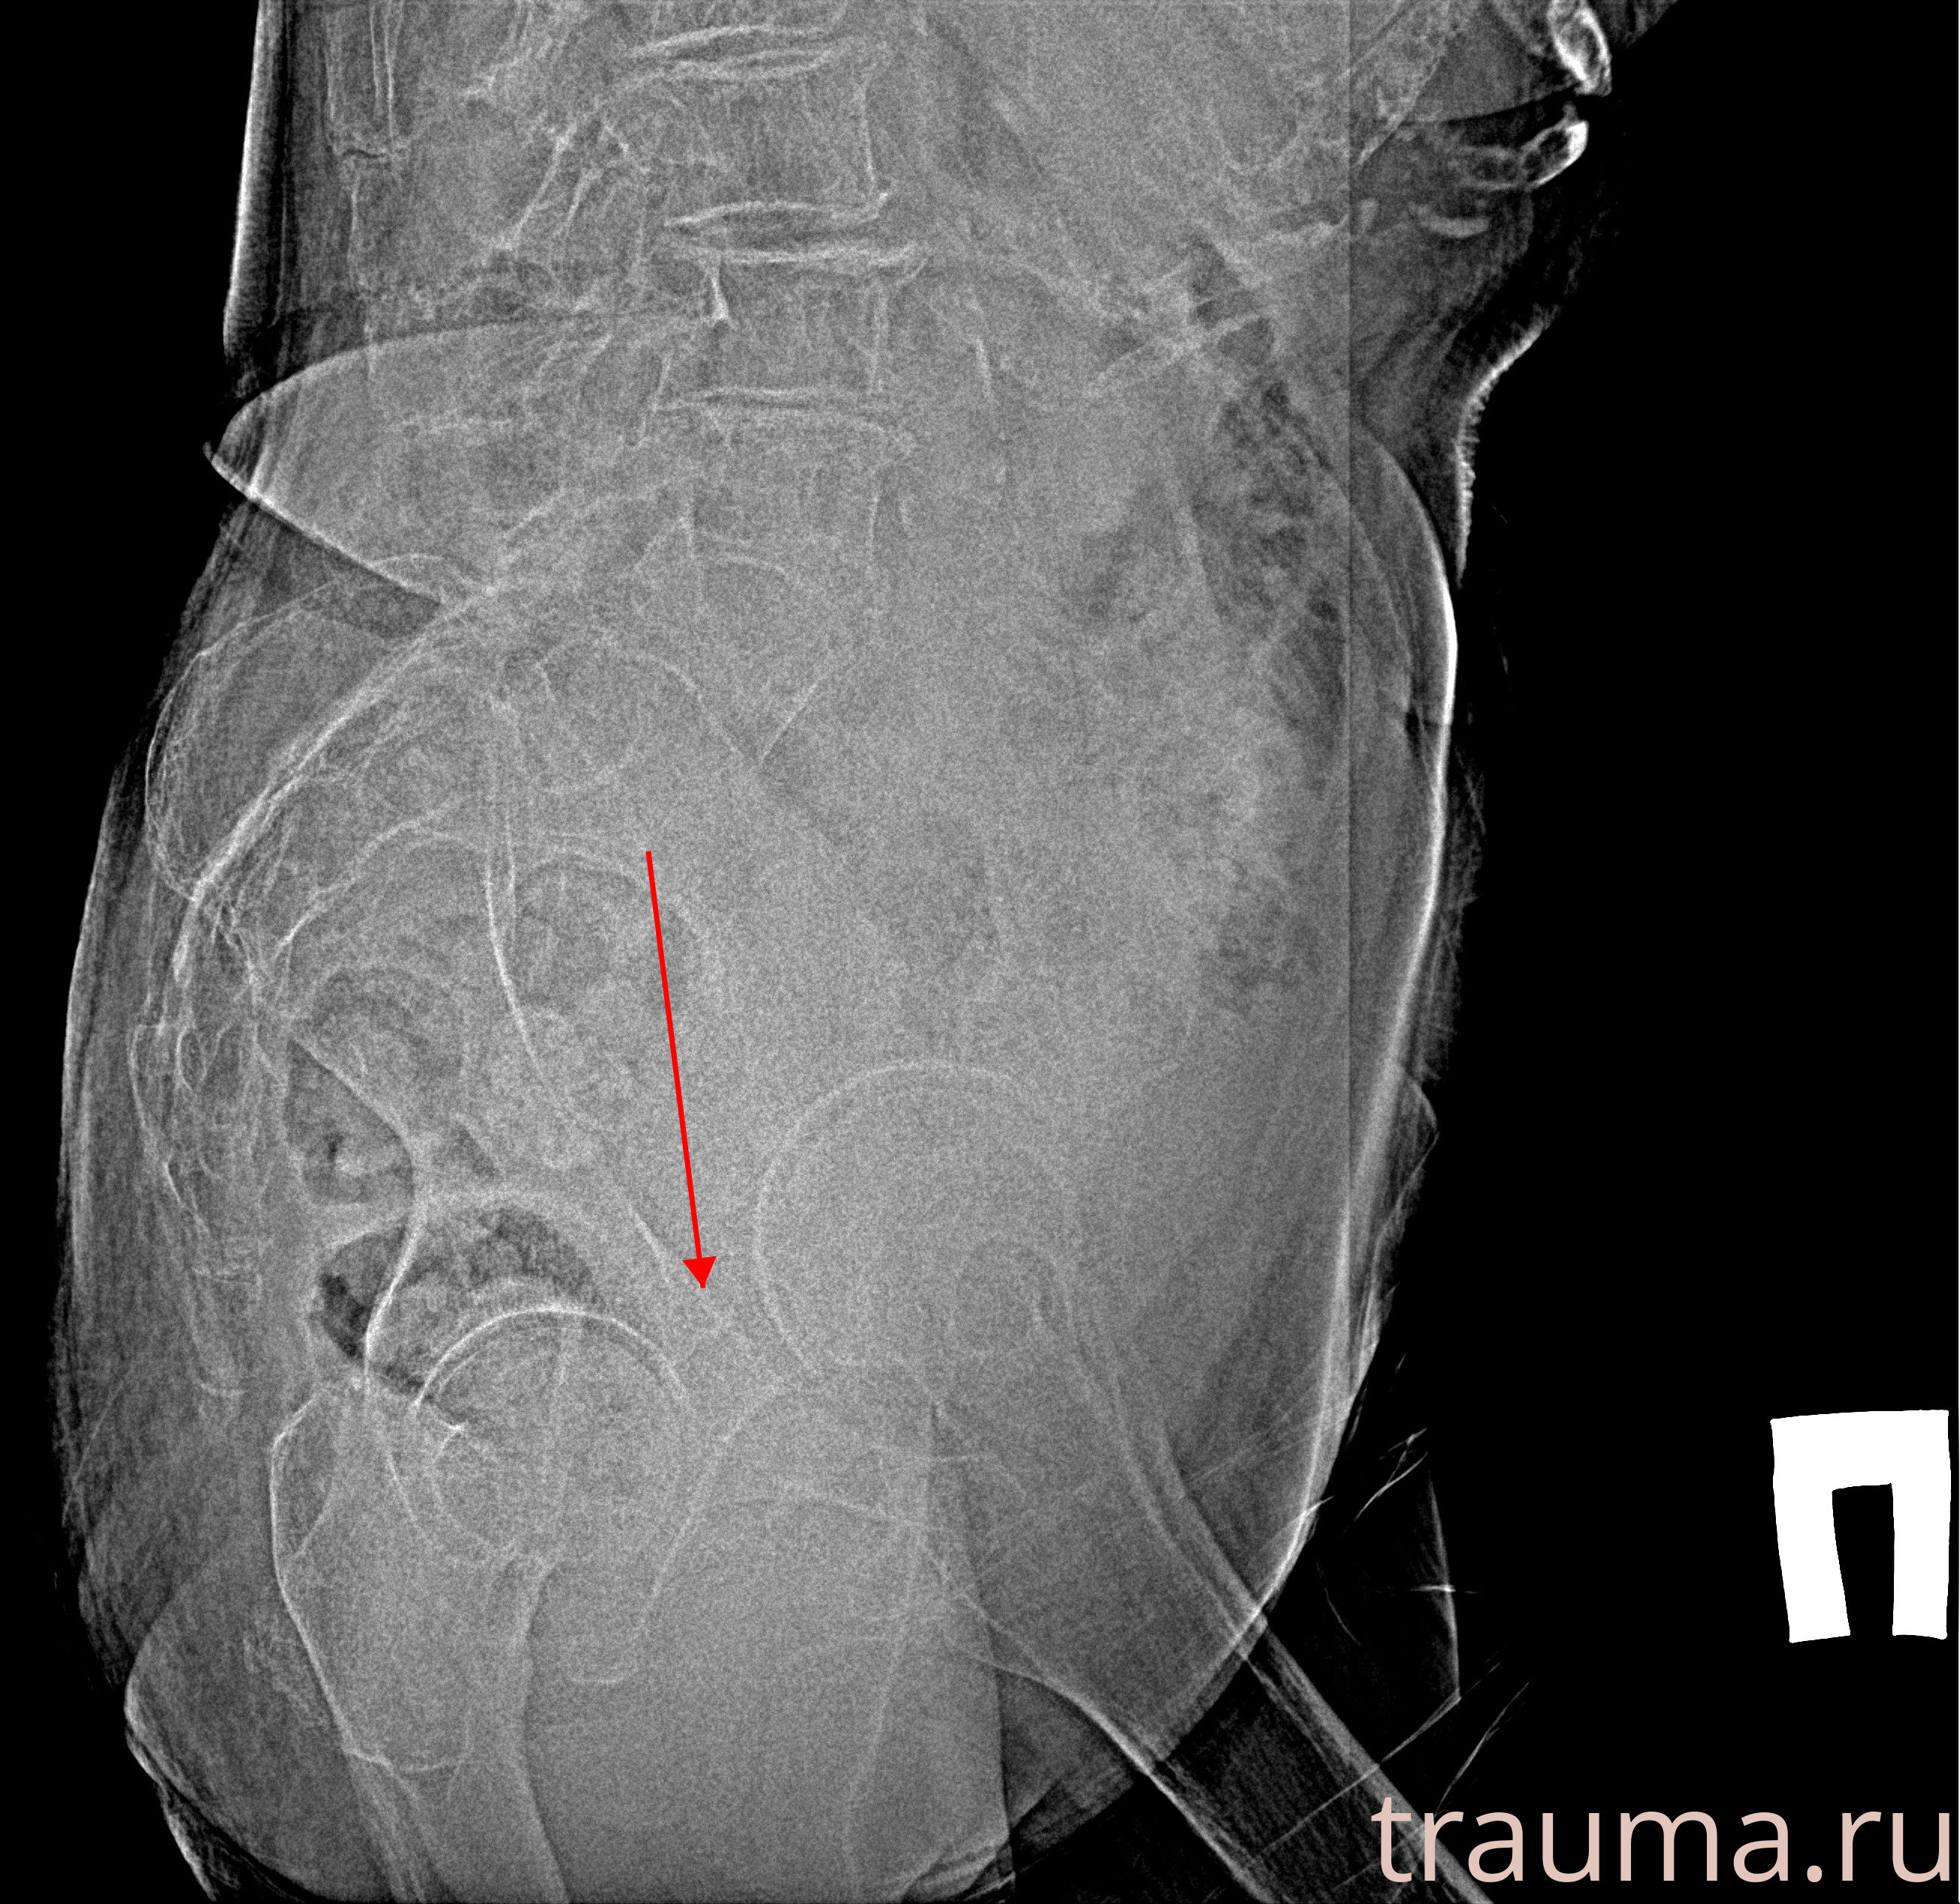

Рентгенограммы

Рентген на дому: по вашему адресу приезжает врач-рентгенолог, травматолог-ортопед с мобильным рентгеновским аппаратом, проводит диагностику травмы или заболевания, делает необходимые рентгенограммы, дает рекомендации по дальнейшему лечению. Получить качественные снимки в домашних условиях возможно благодаря уникальной методике, разработанной МосРентген Центром для института  Склифосовского